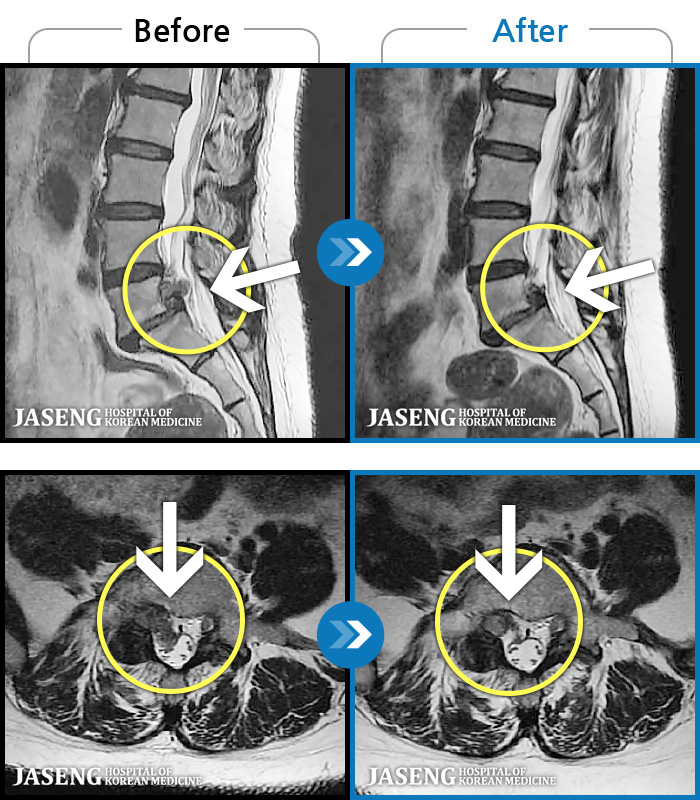

1,237 MRI ũ ʸ Ȯϼ.

1,237